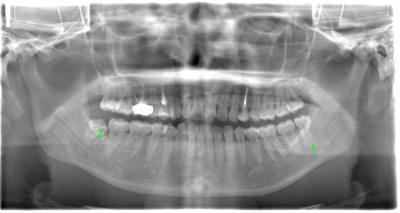

CASE 2

| 年齢・性別 | 30代・男性 |

| 主訴 | 左上下親知らず抜きたい |

| 抜歯期間 | 30分 |

| 抜歯費用 | 約2,500円(保険内) 別途CT撮影で3,000円 |

| 抜歯内容 | 左上下の親知らず抜歯 |

CASE 3

基本情報

| 年齢・性別 | 20代・男性 |

|---|---|

| 主訴 | 左下親知らず抜きたい |

| 親知らずのはえ方 | 半埋伏 |

| 抜歯内容 | 左下の半埋伏親知らず抜歯 |